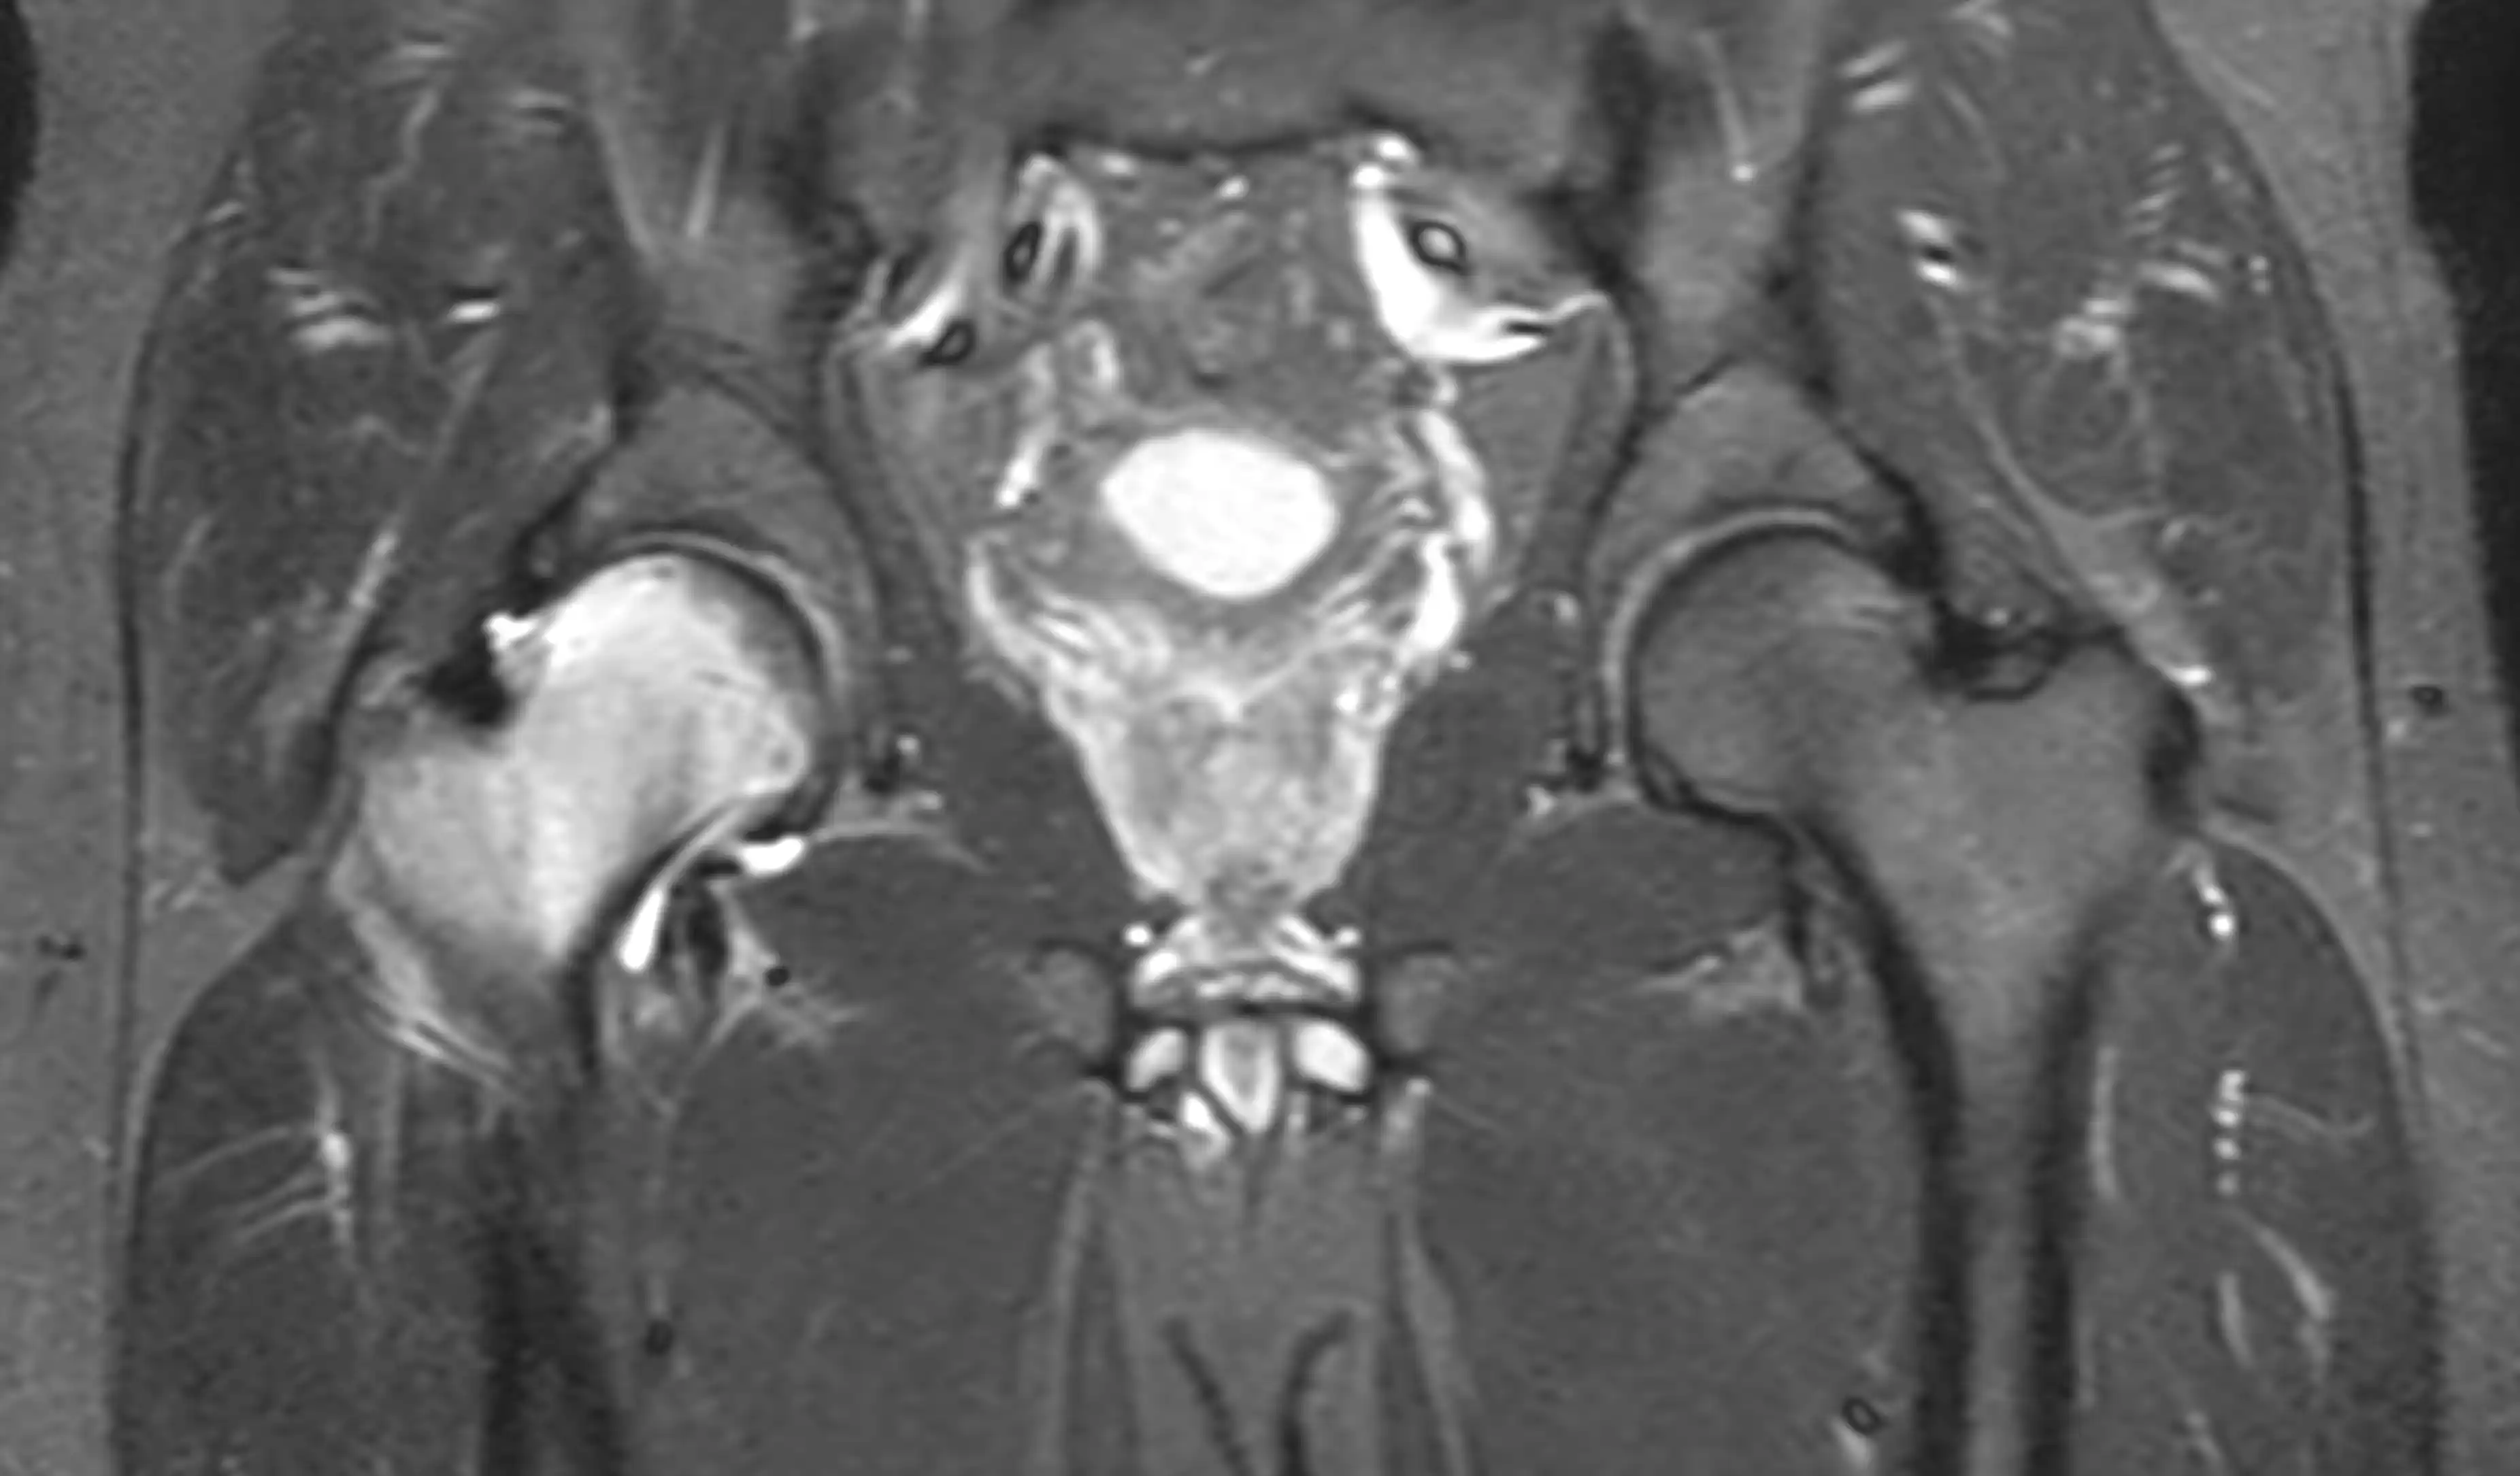

МРТ кульшових суглобів — це сучасний та високоточний метод обстеження, який дозволяє детально оцінити стан кульшових суглобів, кісток, хрящів, зв’язок, м’язів та навколишніх м’яких тканин.

Магнітно-резонансна томографія допомагає виявити причини болю в тазостегновому суглобі та діагностувати різні захворювання без використання рентгенівського випромінювання.

Що показує МРТ кульшових суглобів

МРТ дозволяє виявити:

- артроз кульшового суглоба

- запальні процеси

- ушкодження хряща

- асептичний некроз головки стегнової кістки

- травматичні ушкодження

- новоутворення

- патології м’яких тканин

- зміни зв’язок і сухожиль